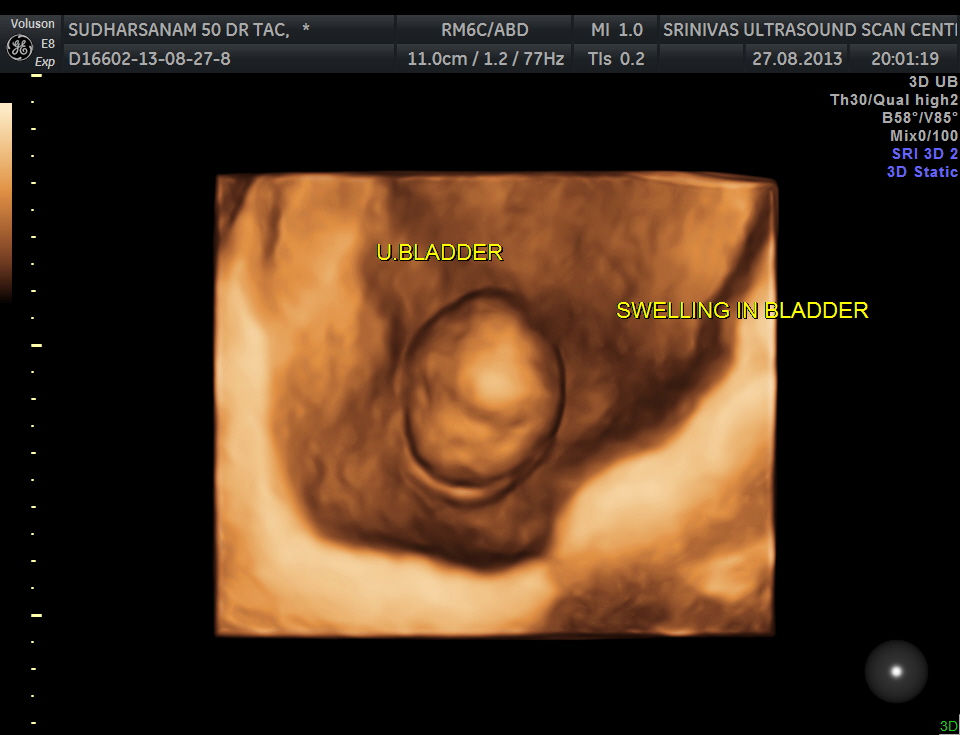

The urinary bladder showed the following :

given below are few other reconstructions

The patient was seen by the urologist and an IVP was done , which proved the diagnosis of orthotopic ureterocele . (a ureterocele entirely within the bladder.)